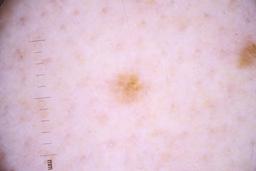

ISIC_4077341

- Challenge 2020: Training

- IP_1969685 IL_9238622

Clinical

| diagnosis_1 | Benign |

| diagnosis_confirm_type | serial imaging showing no change |

| image_type | dermoscopic |

Showing first 50 images.